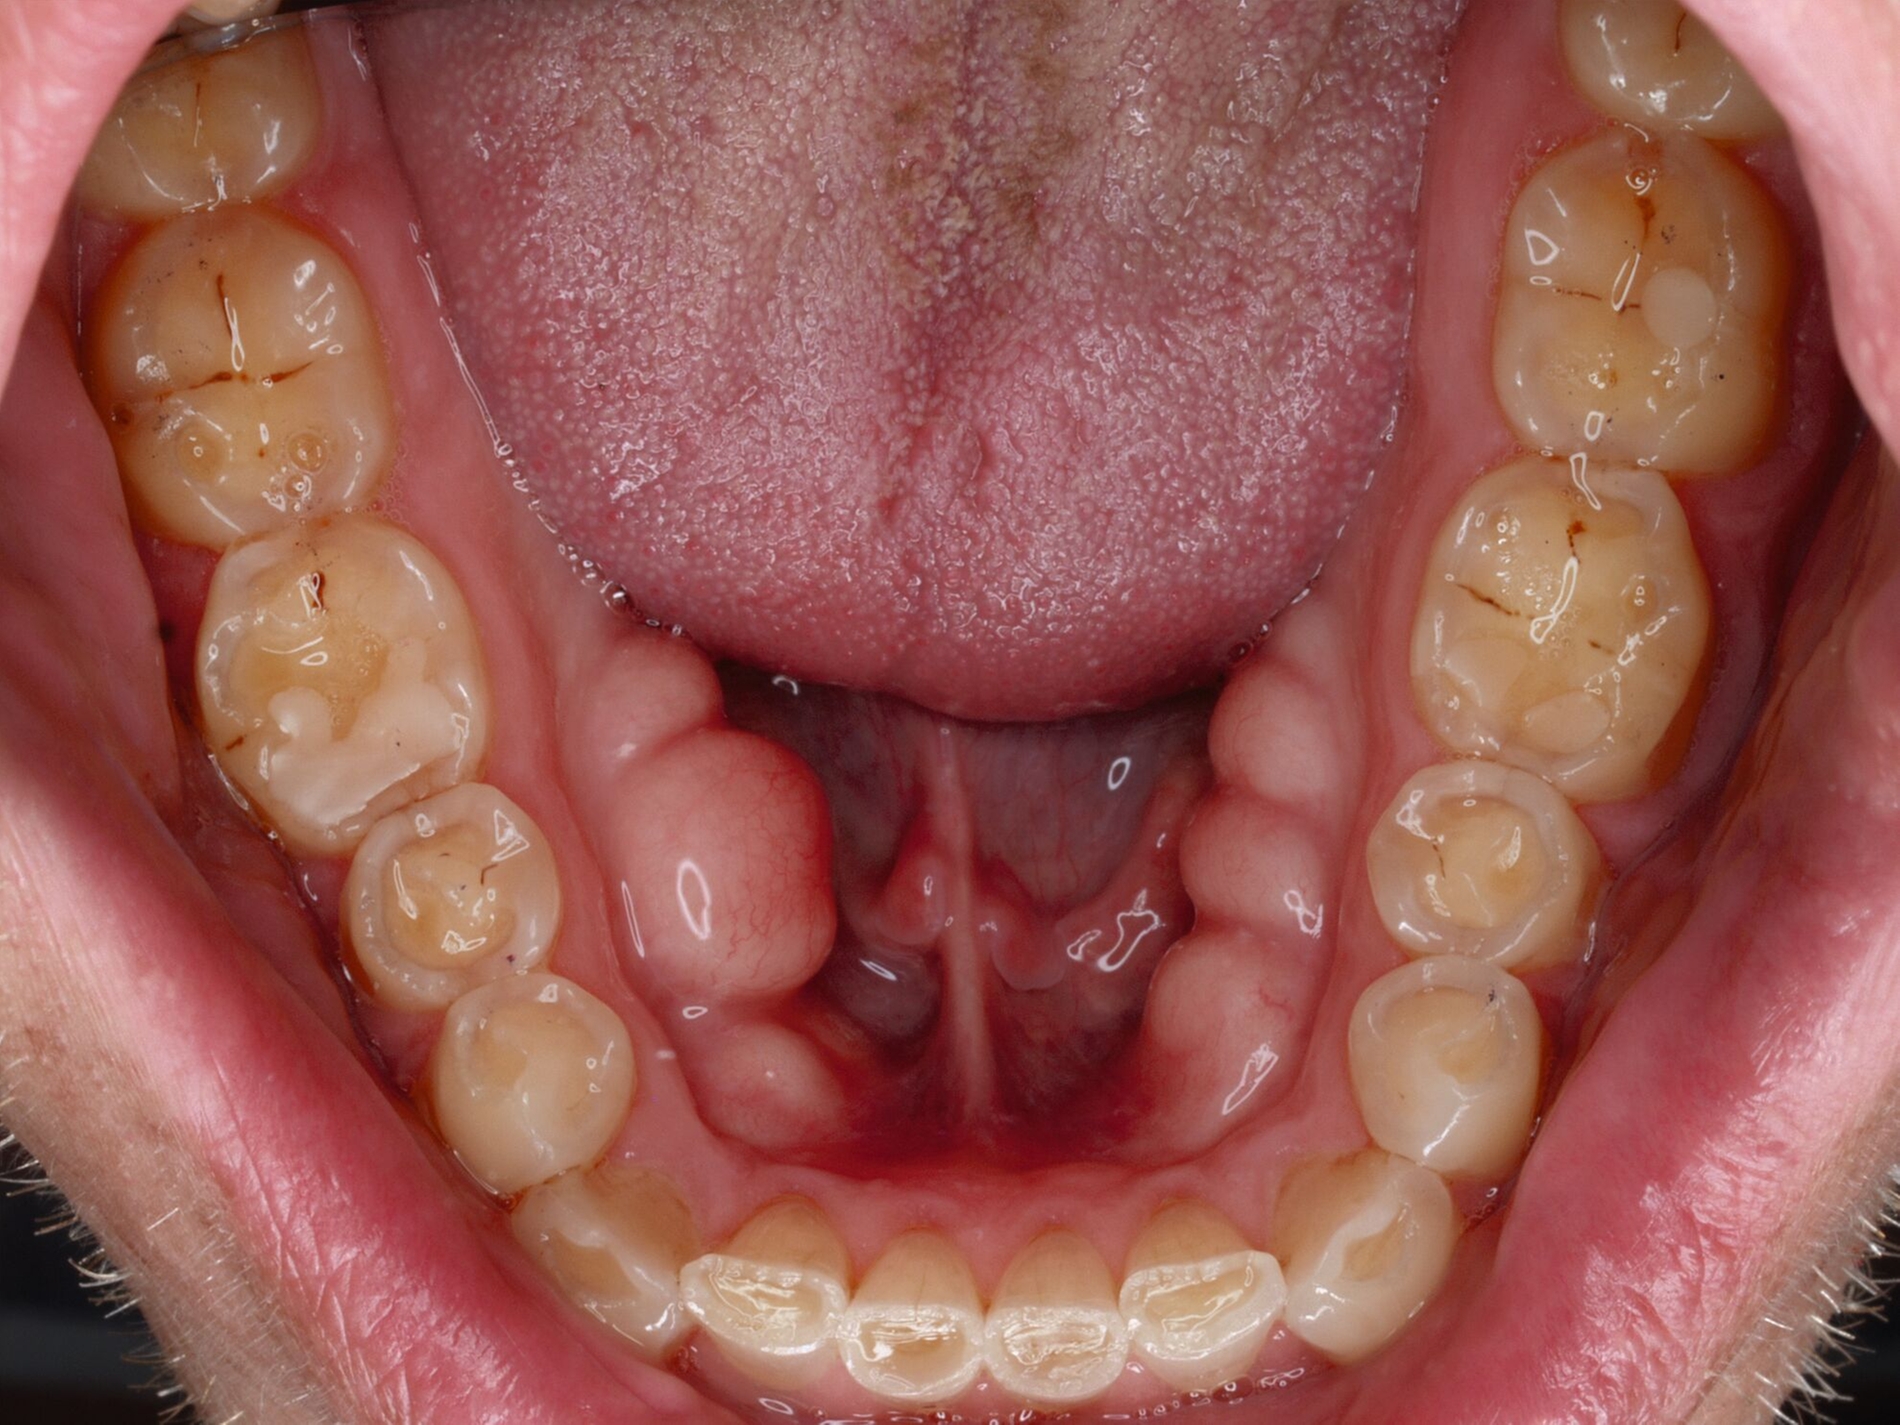

Das unter Beteiligung des Autors entwickelte Tooth Wear Evaluation System (TWES) 2.0 [Wetselaar et al., 2020] identifiziert per Screening Patienten mit erhöhten Verschleißwerten, vergleichbar mit dem PSI in der Parodontologie oder dem CMD-Kurzbefund. Bei auffälligen Werten folgt ein differenzierter Zahnverschleiß-Status einschließlich der Erfassung oraler und vestibulärer Substanzverluste [Wetselaar et al., 2016 sowie von Pathologie-Symptomen und einer strukturierten Diagnose [Tonetti und Sanz, 2019; Wetselaar, 2020]. Den Einsatz in der Praxis illustriert der in den Abbildungen beschriebene Patientenfall aus dem CMD-Centrum Hamburg-Eppendorf.

Zahnverschleiß-Status

Im Unterschied zum Zahnverschleiß-Screening wertet der Zahnverschleiß-Status den höchsten Verschleißgrad pro Zahn aus, und zwar okklusal/inzisal, oral und vestibulär (Abbildungen 4b und 4c, Tabelle 1). Wichtig für die Planung therapeutischer Maßnahmen ist die Frage, welche Zähne okklusal in Kontakt stehen, denn die Behandlung von Zähnen mit erheblichem Zahnverschleiß lässt keinen weiteren Substanzverlust zu und erfordert bei Zähnen in Kontakt absehbar eine Erhöhung der vertikalen Dimension der Okklusion.

Der Zahnverschleiß-Status erfasst auch zehn Kriterien, die nach der Literatur Anzeichen eines pathologischen Geschehens sind. Als pathologisch wird Zahnverschleiß demnach eingeordnet, wenn bei Grad 3 zusätzlich mindestens ein Pathologie-Kriterium vorliegt (Abbildung 6).

Ergänzt wird der Zahnverschleiß-Status durch 20 Merkmale, die jeweils chemischen und mechanischen Ursachen zugeordnet sind und in der summativen Auswertung zeigen, welche Ursachen offensichtlich dem Geschehen zugrunde liegen. Dies ist auch bei vermeintlich eindeutigen Fällen hilfreich, da zuweilen mehrere Faktoren ineinandergreifen, die dann möglichst alle abzustellen sind, bei erheblichem oder extremem pathologischem Zahnverschleiß einhergehend mit einer eventuellen restaurativen Therapie.

Wichtig für das Therapiekonzept ist zudem der Umfang des Zahnverschleißes. Die Auswertung unterscheidet daher lokalisierten und generalisierten Zahnverschleiß.

Im Beispiel ist daher die Diagnose ein generalisierter erheblicher und lokalisierter moderater pathologischer Zahnverschleiß überwiegend mechanischer und zudem chemischer Ursache. Die sich daraus ableitende Erkenntnis ist, dass in allen Sextanten Zähne freiliegende Dentinkerne aufweisen (generalisierter moderater Zahnverschleiß), dass darüber hinaus Zähne erheblich geschädigt und somit gefährdet sind, dass Merkmale eines pathologischen Geschehens bestehen – und dass als Ursache neben dem dominierenden Bruxismus ein Säureeinfluss hinzukommt.

Auch wenn Restaurationen nach Möglichkeit vermieden werden sollten, ist deren Verfügbarkeit für die Betroffenen individuell höchst wichtig, weil sie bestehende Schmerzen beseitigt, die verlorengegangene Kauleistung wiederherstellt und ästhetische und nicht zuletzt auch phonetische Einschränkungen aufhebt. Bei dem in den Abbildungen beschriebenen Fall korrelierte der erhebliche Zahnverschleiß mit der Lokalisation der Zahnschmerzen des Patienten. Direkte Restaurationen mit Kompositen hatten keinen Bestand. Die durchgeführte restaurative Behandlung hingegen hat Bestand, die Schmerzen waren danach umgehend verschwunden und sind seit zehn Jahren nicht wiedergekehrt.